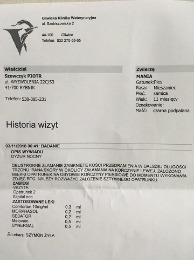

potwierdzenie od weterynarza